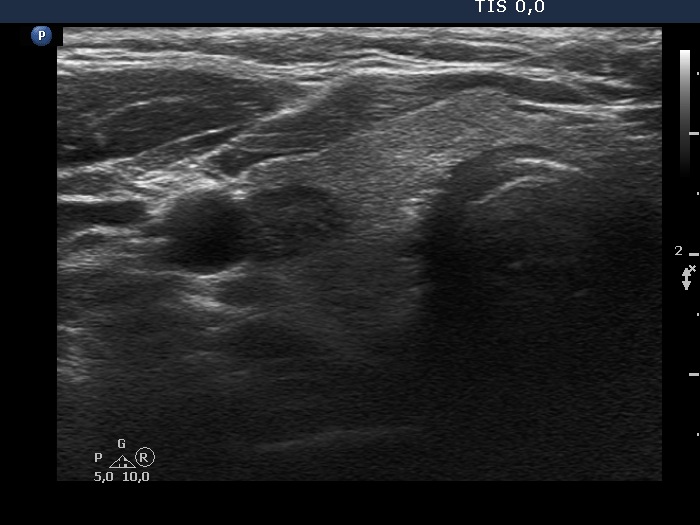

100 consecutive cases of papillary cancer - case 075 (ultrasonographic picture 3)

Upper part of the right lobe, transverse scan. There is a hypoechoic nodule in the lateral part of the lobe.